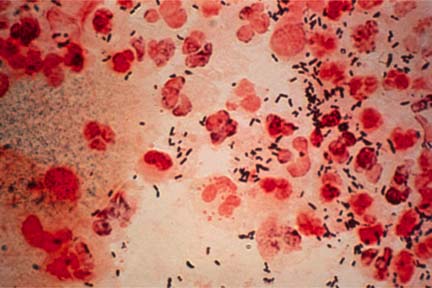

La gonorrea cerca de no ser tratable

Dentro de dos años, 2015, la gonorrea puede ser intratable en Reino Unido si no se hace algo al respecto.

Dentro de dos años, 2015, la gonorrea puede ser intratable en Reino Unido si no se hace algo al respecto. Esta es la advertencia de una especialista inglesa en el área de transmisión sexual quien este martes informó que la resistencia a antibióticos está convirtiendo la enfermedad intratable.